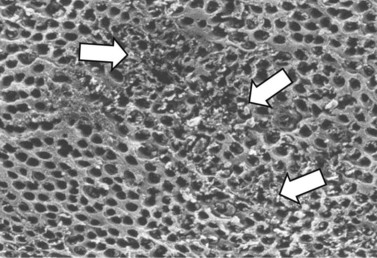

Fig. 10.30 Scanning electron microscopy image of carious dentin lining a pulp chamber that contains necrotic pulp. Many areas have localized loss of integrity of intertubular dentin (arrows).

(Reproduced from Dacre et al55 with permission of The Veterinary Journal.)